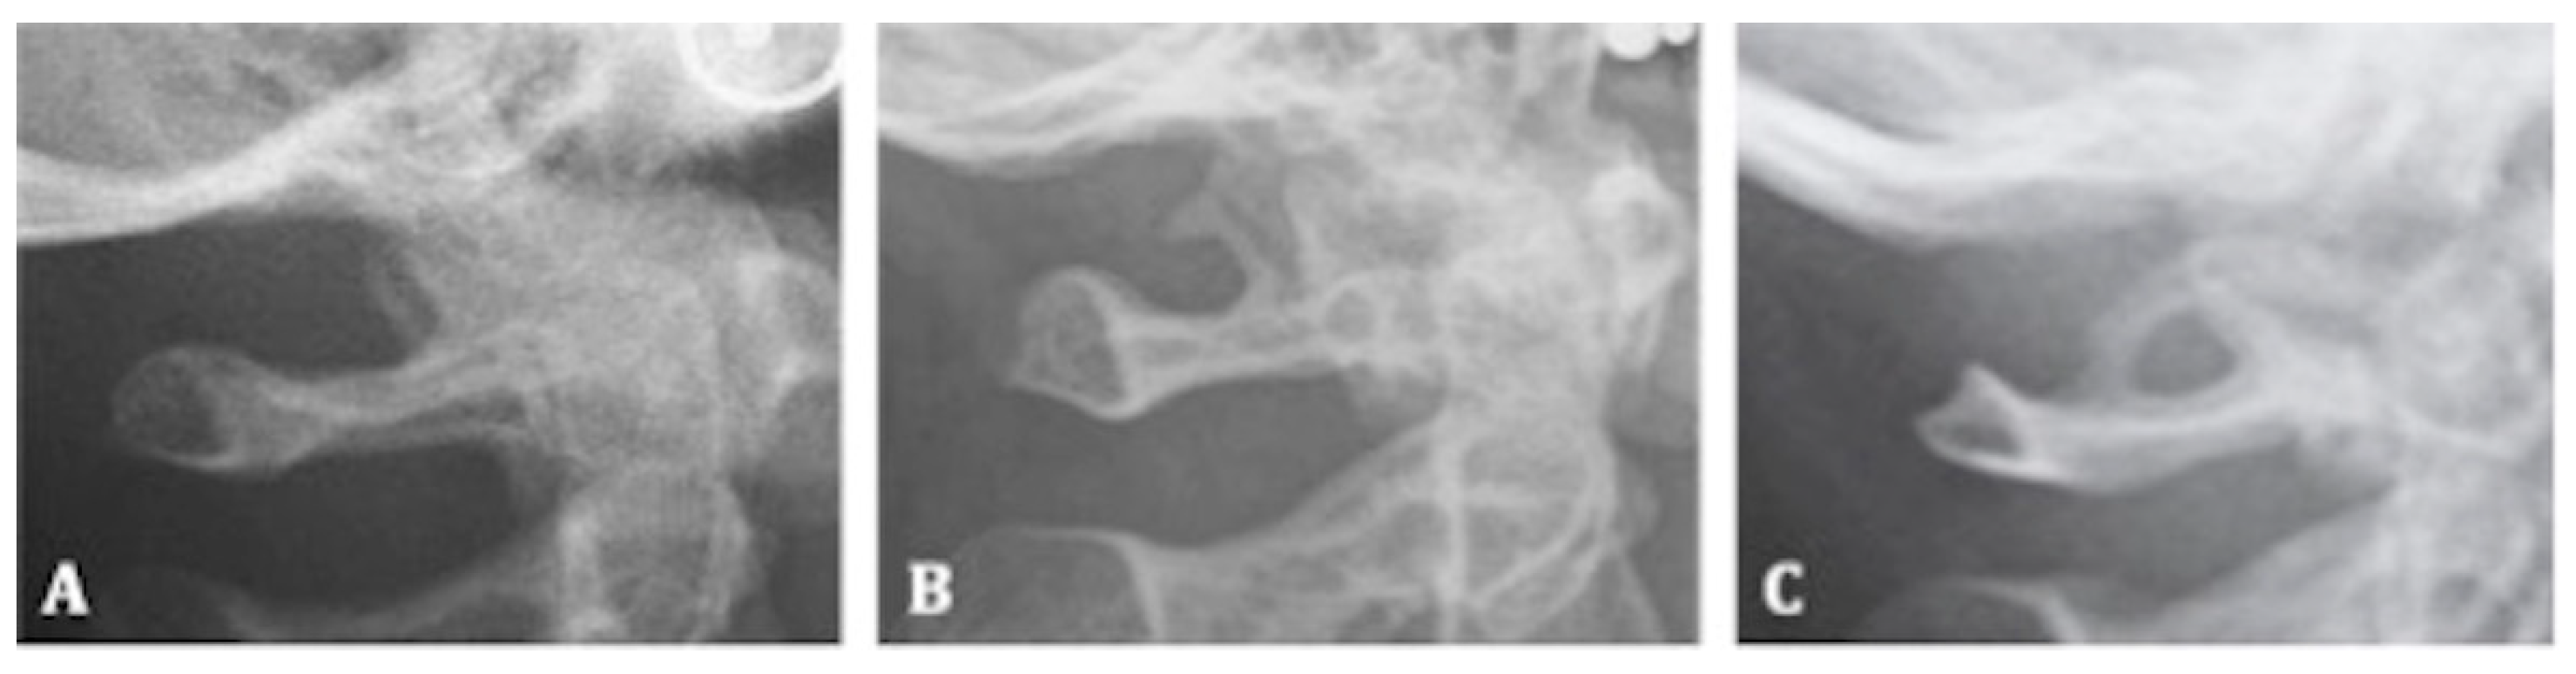

- Class III (complete calcification): when the diaphragm of the sella is evident on the radiograph (Figure 2A–C).